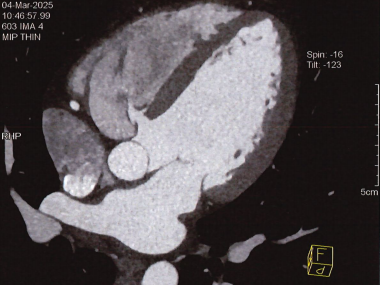

术前CT全方位判断室缺位置、形态及大小